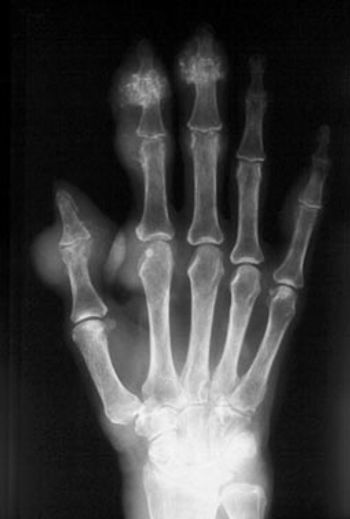

What is your diagnosis from this hand X-ray?